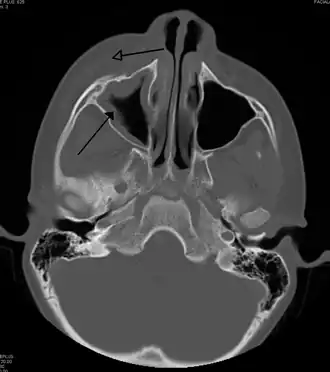

MRI image showing sinusitis. Edema and mucosal thickening appear in both maxillary sinuses. -

Maxillary sinusitis caused by a dental infection associated with periorbital cellulitis -